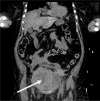

An elderly patient, who was being treated for therapeutic enoxaparin for a couple of days due to suspected deep vein thrombosis, was admitted to hospital following a collapse and severe abdominal pain. She was in hypovolemic shock and was fluid resuscitated. Ultrasound scan and computed tomography (CT) scan showed a large pelvic hematoma. Radiologists also suspected a possibility of bleeding from inferior epigastric artery following a CT angiogram. The patient was stabilized and transferred to intensive care unit (ICU) for further hemodynamic supports and close monitoring. The patient was then transferred back to the general ward when she was stable. She was managed conservatively as there were no more signs of active bleeding. Unfortunately, she died of recurrent bleeding three days after ICU discharge.